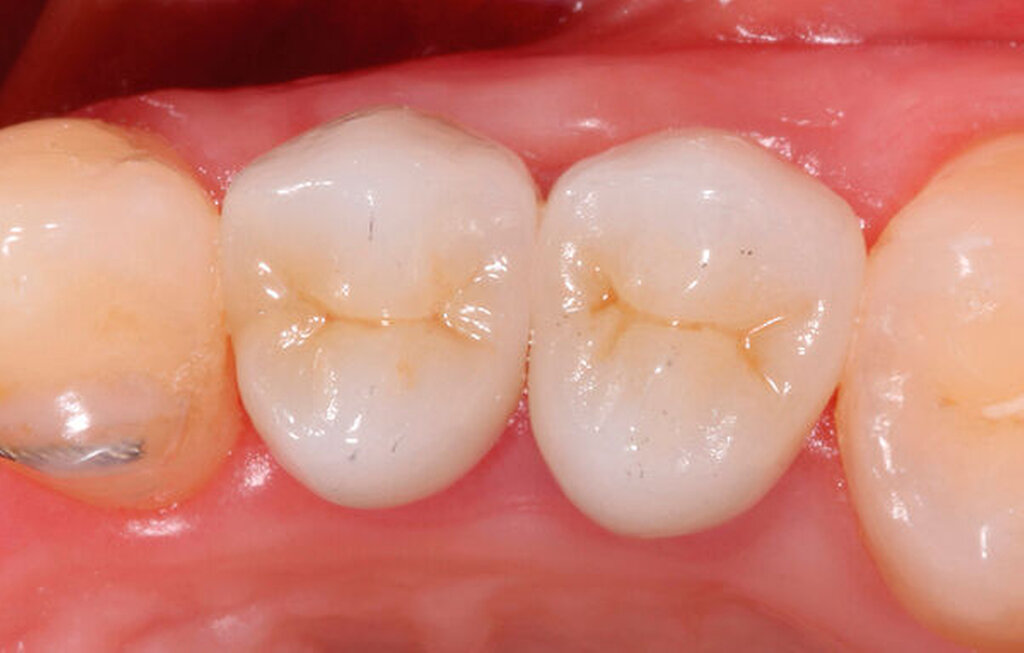

Als Hilfsmittel, die die Zugkräfte auf die betroffenen tief zerstörten Zähne übertragen können, eignen sich spezielle Magnet- oder Gummizug-Systeme (zum Beispiel Neodym-Scheibenmagnete; TMC Extrusion, Komet GmbH) (Abbildungen 12 und 13). Bei den Magnetsystemen ist in der Regel ein Abstand von 0,5 bis 2 mm zum Kontermagneten über einen Abstandshalter nötig. Der Kontermagnet wird in einer Tiefziehschiene oder in ein entsprechendes Methacrylatprovisorium mit Abstützung an den Nachbarzähnen einpolymerisiert. Die Zugkraft beeinflusst die Art der Extrusion. Kräfte mit circa 0,3 N verursachen eine verzögerte Extrusion um etwa 1 mm pro Woche. Die forcierte Extrusion erfordert mindestens 0,5 N, um eine Extrusion von mehr als 1 mm pro Woche zu bewirken [Krastl, 2004].

Die Extrusionzeit beträgt zumeist vier bis acht Wochen, wobei eine initiale, meist länger dauernde Phase der Zahnlockerung keine merkliche Bewegung verursacht und in einer sekundären kürzeren Phase von wenigen Tagen die Extrusionsbewegung stattfindet. Eine teils langwierige Retentionsphase von mindestens vier bis acht Wochen schließt sich an. Vorteilhaft sind das intakte Weichgewebe und die äußerst einfache Hygienefähigkeit.